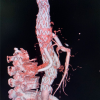

手术前CT三维重建诊断为胸腹主动脉瘤。

经血液外科医生分析病情,为患者制订了胸腹主动脉覆膜支架腔内隔绝术+分支支架内脏血管重建的手术方案。因手术涉及支架改造,过程复杂,术中由血液外科副主任医师舒小军和主治医师李正飞各带领一组医生同时进行。最终手术历时5个半小时,实现了胸腹主动脉瘤腔内隔绝,并重建了双肾动脉和肠系膜上动脉。目前,患者已脱离危险,能下床活动。

手术后一周CT复查提示胸腹主动脉瘤治愈。